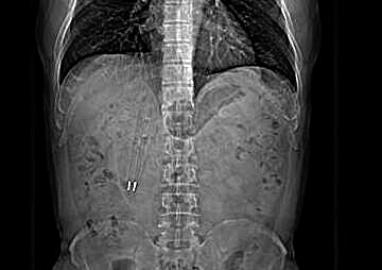

CT中能清晰看到亮闪闪的笔尖,右上为体内取出的两支圆珠笔

家住昆山的王先生,今年50岁,今年2月份,他去昆山中医院体检时心头一紧,因为体检结果显示,他的十二指肠部位有明显异物。其后,王先生赶紧做了个CT,医生发现,王先生的十二指肠里竟有两个笔状的异物。

王先生体内的笔长约

12厘米,位于十二指肠球降部。中医院医生徐宏伟介绍说,这个笔从口中吞下,经过了食管、胃、幽门,到达了十二指肠,其中有一支笔的笔尖已经戳到了肠壁,由于十二指肠长度和一支笔的长度差不多,笔无法再向下滑。

王先生吞下去的这两支笔都是塑料的,从CT上看,还可以看到笔里的金属弹簧和金属笔尖在闪闪发光。